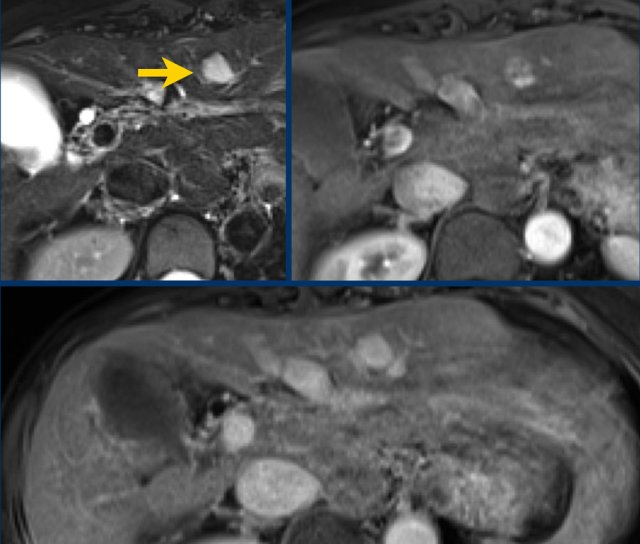

Diffusion restriction

In this patient with cirrhosis the MR-images show an arterially enhancing observation (< 2 cm) in the right lobe (arrow).

As there is no washout or any other major feature observed this should be classified as a LR-3 lesion.

However due to the ancillary finding of diffusion restriction this observation can be upgraded to a LR-4.

This is a difficult topic, since diffusion restriction can also be seen in non-HCC tumors.

If there is doubt between the diagnosis of possible HCC and another type of malignancy a diagnostic biopsy can be considered.